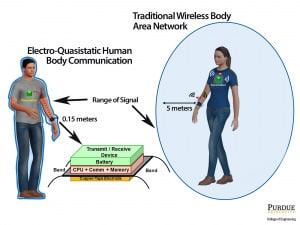

Il team di ricercatori ha messo in sicurezza la body network contenendo il segnale all’interno del corpo umano: smartwatch, smartphone, apparecchi biomedicali e sensori vari comunicano tra loro utilizzando come conduttore gli stessi tessuti corporei.

La rete dentro di te. Il segnale elettromagnetico non viene quindi più trasmesso via etere dal bluetooth, ma viene diffuso lungo la pelle e i tessuti adiposi. Queste comunicazioni non possono più essere intercettate da remoto, ma solo da dispositivi fisicamente a contatto con il corpo dell’interessato: al momento in

Gli scienziati della Purdue hanno messo a punto un sistema di comunicazione, che utilizza particolari circuiti elettrici, che richiede pochissima energia per funzionare e che permette di realizzare una body network completamente sicura: a fare da “punto di accesso” per i collegamenti da remoto (per esempio per acquisire i parametri misurati) è, in questo caso, lo smartphone della persona monitorata (smartphone che dovrebbe comunicare in modo sicuro, almeno lui, con l’esterno).